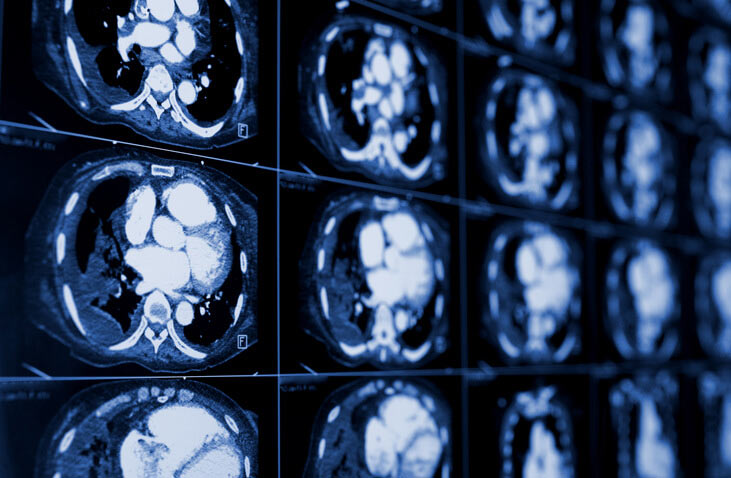

Mesothelioma is a type of cancer caused almost exclusively by asbestos exposure. It develops in the thin layer of tissue that covers most of your internal organs, called the mesothelium. When doctors suspect this condition, a Computed Tomography (CT) scan is usually among the first imaging tests ordered because it offers highly detailed cross-sectional images of the chest, abdomen, or other affected areas.

A CT scan helps visualize organs, soft tissues, bone, and blood vessels with much greater clarity than a standard X-ray. For mesothelioma, it's invaluable for initial detection, staging, and monitoring the disease's progression. It can pinpoint abnormalities that might suggest the presence of this challenging cancer.

When radiologists examine a CT scan for signs of mesothelioma, they're looking for several characteristic findings. These indicators can vary, but certain patterns are highly suggestive of the disease. Here are some of the most common signs:

- Pleural Thickening and Plaques: This is a hallmark sign. The pleura, the lining of the lungs, can become unusually thick and irregular. Calcified pleural plaques, though benign, often indicate past asbestos exposure and can be a precursor or co-occurrence with mesothelioma.

- Pleural Effusion: This refers to the buildup of fluid between the layers of the pleura. While many conditions can cause pleural effusion, a persistent or recurrent effusion, especially when unilateral (on one side), is a red flag for mesothelioma.

- Nodules and Masses: Small lumps (nodules) or larger growths (masses) on the pleura are direct signs of tumor development. These can be singular or multiple and often appear irregular.

- Shrinkage of Lung (Volume Loss): As the tumor grows and encases the lung, it can lead to a decrease in the lung's volume, often pulling structures like the mediastinum (the space between the lungs) towards the affected side.

- Invasion of Adjacent Structures: In advanced cases, the tumor might show signs of spreading into nearby tissues, such as the chest wall, diaphragm, or even the heart's outer lining.

On a CT scan, these signs of mesothelioma often present in a diffuse and somewhat aggressive manner. You might see a "rind-like" or "sheet-like" thickening that covers a large area of the pleura, rather than a localized mass. The irregular nature of the thickening and the presence of nodularity are key differentiators from benign conditions. Doctors are trained to recognize these subtle yet significant patterns when evaluating a Mesothelioma On CT Scan.